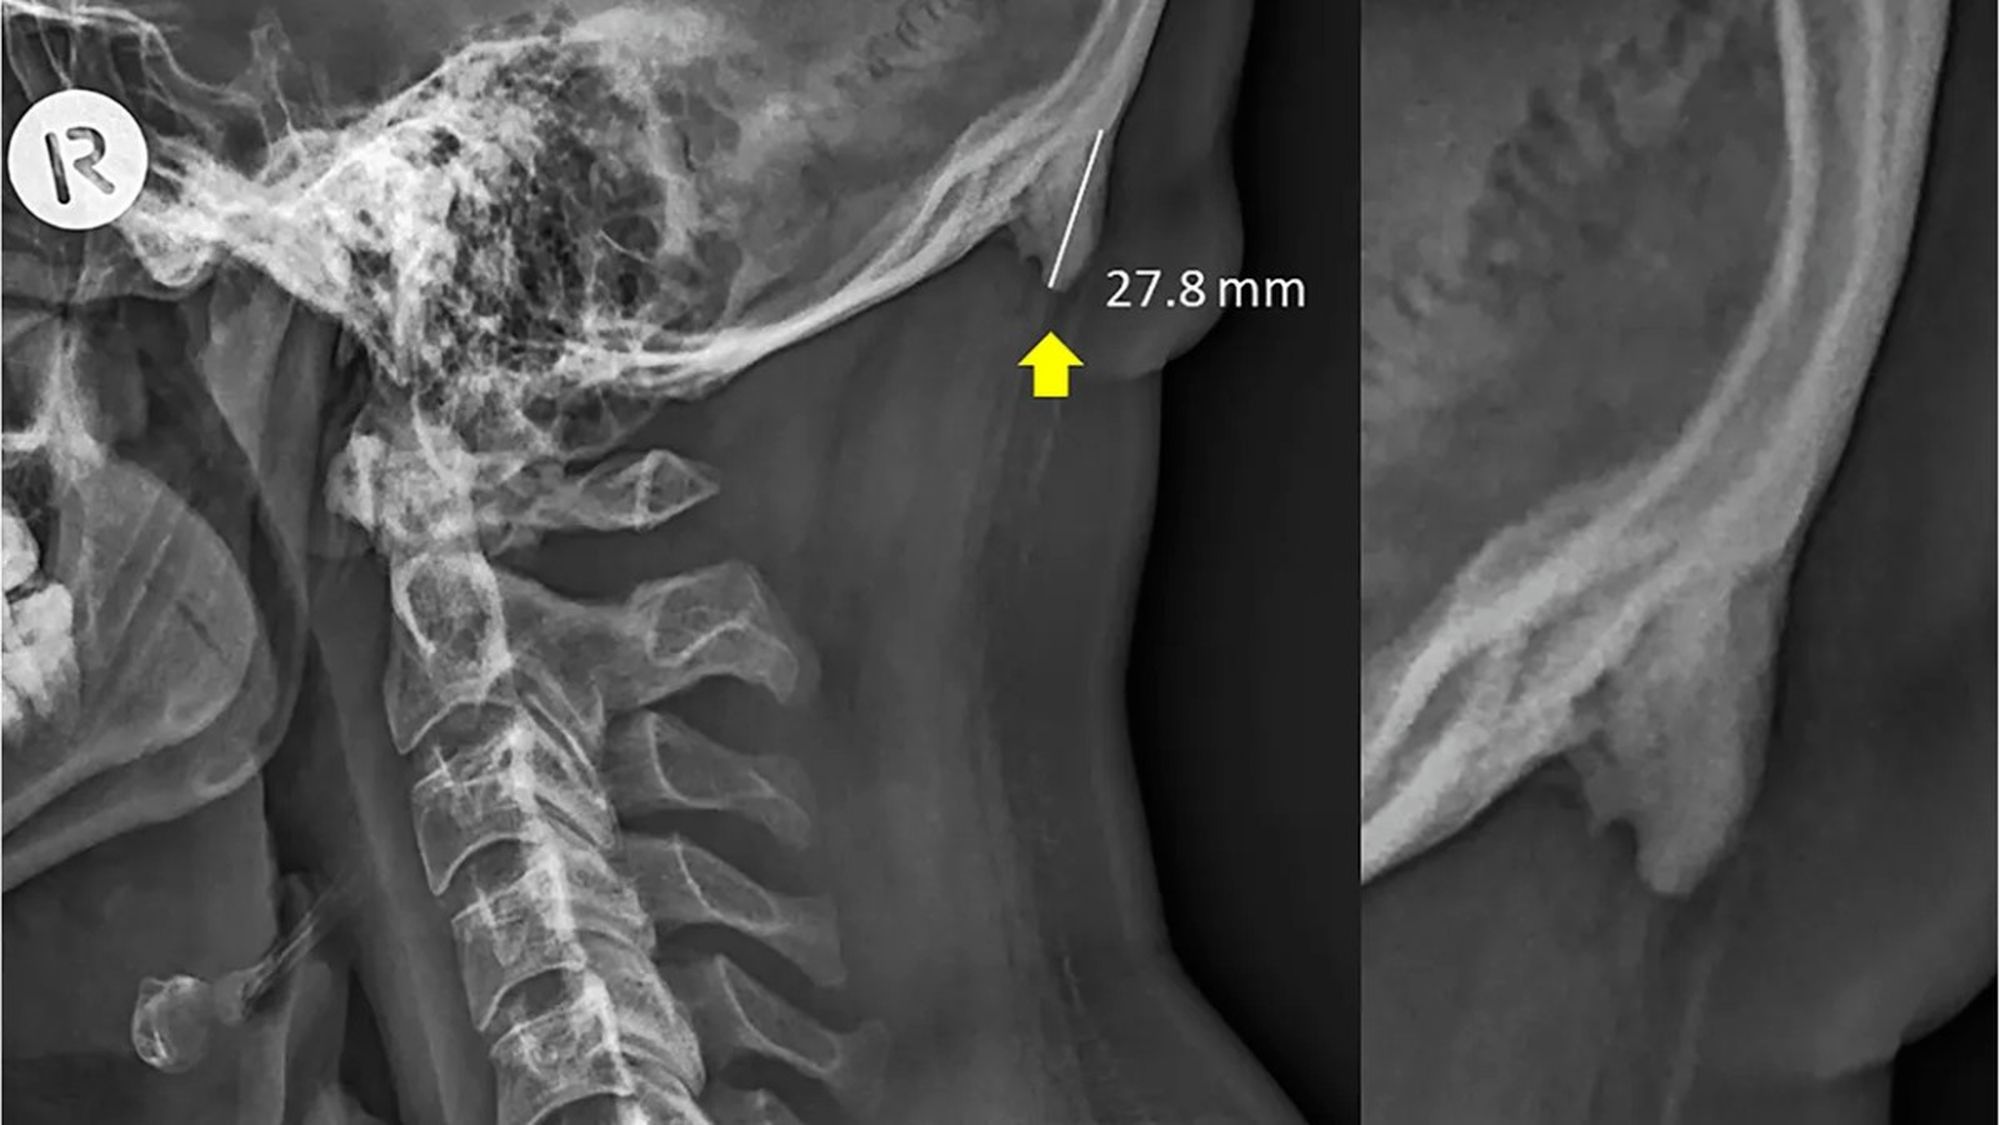

Söz konusu kemik uzantısını ortaya çıkaran veriler, 3 yıldır boyunca Avustralya'nın Queensland bölgesinde çekilen X-ışını taramalarından geliyor. Bu taramalarda, söz konusu çıkıntıların da bulunduğu bölgenin fotoğrafları çekildi. Normalde bu kemik uzantıları çok şaşırtıcı değil ve yaşlılarda görülüyor; çünkü yıllar yılı hayatta kalıp, boyun kaslarına yük bindirince, bu kemikler de ilerleyen yaşlarda gelişebiliyor. Ancak şaşırtıcı olan, genç yetişkinlerde de bu kemiklerin gözükmeye başlamış olması. Hem de kimi zaman bu genç yetişkinlerde yaşlılardan bile daha uzun kemikler görülüyor!

Genişlemiş dış oksipital çıkıklık (İng: external occipital protuberance) adı verilen bu durum eskiden gençlerde çok nadiren görülmekteydi. Ancak 2018 yılında Clinical Biomechanics dergisinde yayımlanan bir çalışma, bunun gençlerde daha sık görülmeye başlandığını ve sebebinin genetik veya enflamasyon gibi faktörler olmadığını; daha ziyade mekanik yük binmesi sonucu olduğunu gösterdi.

İşte bundan yola çıkan araştırmacılar, nihayetinde 18-86 yaş arası insanlara ait 1200 X-ışını taramasını inceleyerek, bu kemiklerin popülasyonun %33'ünde bulunduğunu ve şaşırtıcı bir şekilde artık yaş ilerledikçe bu kemiklerin kısaldığını gösterdiler! Bu keşif, yerleşik bilimsel bilgilerimizle fazlasıyla zıt. Çünkü normalde bu çıkıntılı kemiklerin ilerleyen yaşlarda daha da uzadığı düşünülmekteydi! Shahar şöyle diyor:

Biyomekanik alanında çalışmalar yürüten uzmanlar söz konusu kemik çıkıntısı uzamasının özellikle gençlerde daha sık ve daha belirgin olmasının ana sorumlusunun telefona bakmak için öne eğilen kafaların yarattığı kütle merkezi değişiminin kafataslarında boynuz-benzeri uzantıların gelişmesine neden olduğunu düşünüyorlar. Kafamızı durmaksızın öne eğince, kafamızın ağırlığını dengeleyen kas grupları, omuriliğimiz hizasından kafanın arkasındaki kaslara doğru kaymaktadır. Bu da, bu yeni pozisyonda yeni kemik, tendon ve ligament gelişimini pekiştirmektedir. Bu da, boynun hemen üzerinde boynuz-benzeri kemiklerin belirmesi anlamına gelmektedir.